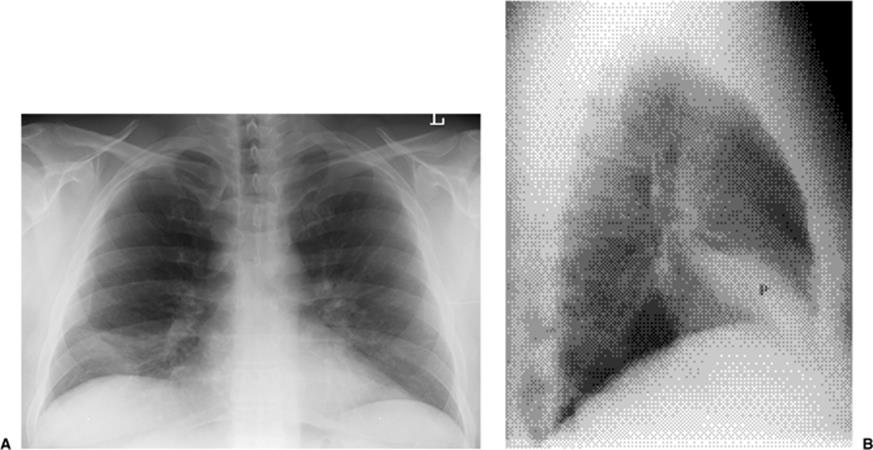

Figure 5.1 Opacity in pneumonia. (A) Posteroanterior and (B) lateral chest radiographs: minimal right basilar opacity, much better seen on the lateral view overlying the heart (P).

Figure 5.2 Opacity in pneumonia. (A) Posteroanterior and (B) lateral chest radiographs: vague retrocardiac abnormality (P) with corresponding increased opacity over the lower thoracic spine on the lateral view (arrows).